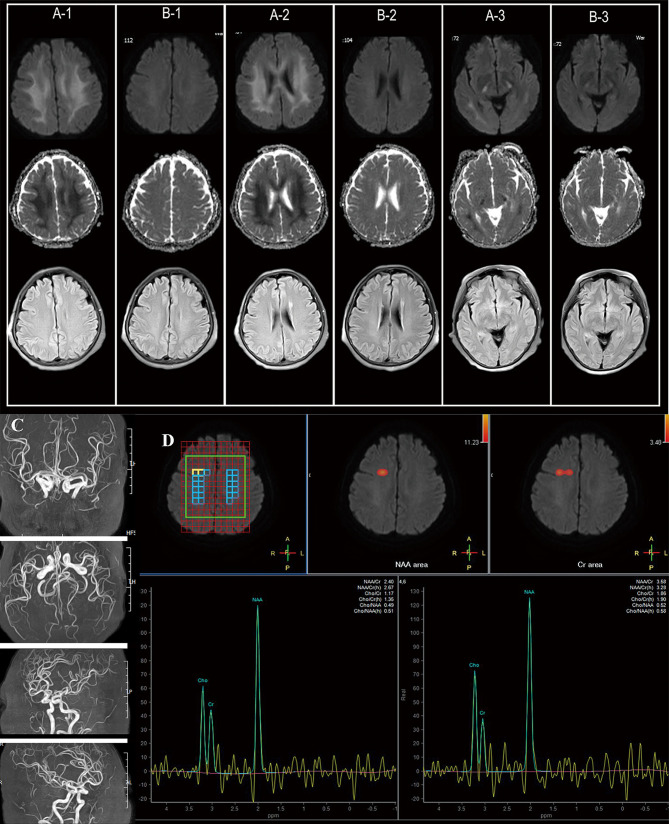

氟乙酰胺是一种常用的惊厥灭鼠剂,可迅速损害神经系统、消化系统和心血管系统,如果摄入,可能导致致命的后果。本研究报告了一名62岁中国妇女的病例,她出现中毒症状,包括言语不清、躁动和癫痫样发作,并伴有胃肠道症状,如呕吐、皮肤瘀伤和轻度肝功能障碍。毒素分析显示她的血液和尿液中存在氟乙酸,扩散加权成像(DWI)显示白质病变,导致罕见的氟乙酰胺中毒诊断。这一诊断促进了治疗的实施,包括维生素K、血液透析、乙酰胺和葡萄糖酸钙。患者随后恢复意识,实验室结果改善,毒性代谢性脑病逐渐消退。该病例强调了考虑具有挑战性神经系统症状的患者药物中毒的重要性,特别是当有潜在的药物摄入史时。准确诊断这些疾病是至关重要的,因为及时和适当的治疗可以显著改善临床结果。

Fluoroacetamide, a commonly used convulsant rodenticide, can rapidly damage the nervous, digestive, and cardiovascular systems, potentially leading to fatal outcomes if ingested. This study reports the case of a 62-year-old Chinese woman who presented with symptoms of intoxication, including slurred speech, agitation, and seizure-like episodes, accompanied by gastrointestinal symptoms such as vomiting, skin bruising, and mild liver dysfunction. Toxin analysis revealed the presence of fluoroacetate in her blood and urine, and diffusion weighted imaging (DWI) imaging indicated white matter lesions, leading to the diagnosis of rare fluoroacetamide poisoning. This diagnosis facilitated the administration of treatments including vitamin K, hemodialysis, acetamide, and calcium gluconate. The patient subsequently regained consciousness, with improvements in laboratory results and gradual resolution of toxic-metabolic encephalopathy. This case highlights the importance of considering drug poisoning in patients with challenging neurological symptoms, particularly when there is a potential history of drug ingestion. Accurate diagnosis of such conditions is crucial, as timely and appropriate treatment can significantly improve clinical outcomes.